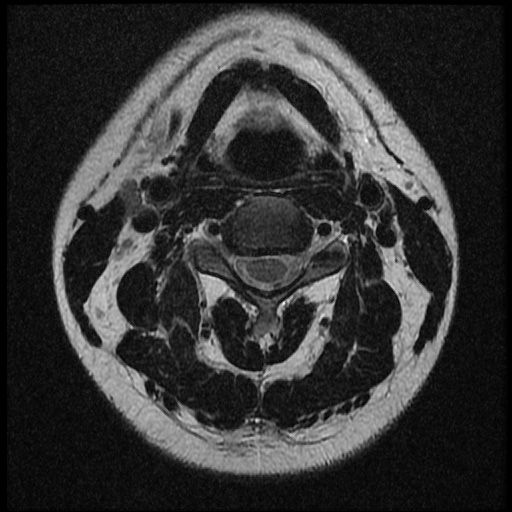

근대 21년 사고 이후부터 목쪽이 계속 아픈 상태 여서 사고로 인한 급성인지 우연이 겹친 민성 디스크 인지 확인하고 싶습니다~

이 MRI 사진은 21년도 사고 당시 찍은 MRI 사진 입니다. 확인 부탁드립니다~

전체 mri를 다 봐여겠지만 보여주신 mri 컷에서는 의미있는 경추 디스크탈출이 보이지 않습니다.